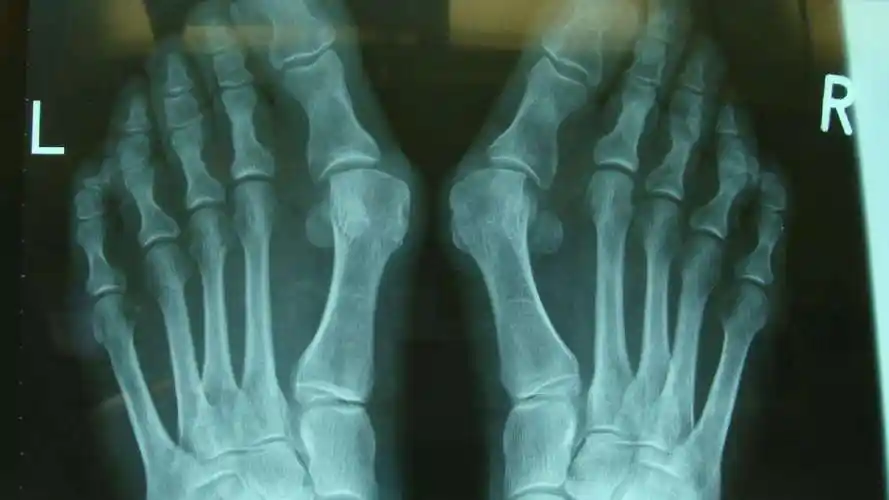

大脚骨scarf akin截骨 - 好大夫在线